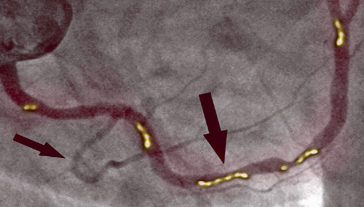

PRIJE TERAPIJE

Na slici lijevo vidimo suženje desne koronarne arterije kod 66-godišnjeg muškarca, dijagnosticirano pomoću invazivne koronarografije. Vidljivo je značajno suženje u proksimalnom segmentu uzrokovano kalcificiranim aterosklerotskim plakom, koji blokira protok krvi.

NAKON TERAPIJE

Na slici desno vidimo očišćenu desnu koronarnu arteriju već bez tragova kalcificiranog aterosklerotskog plaka kod istog pacijenta nakon 1. mjeseca terapije. Nema smrtonosnih naslaga kolesterola. Krv teče slobodno, opskrbljujući kisikom sve organe.